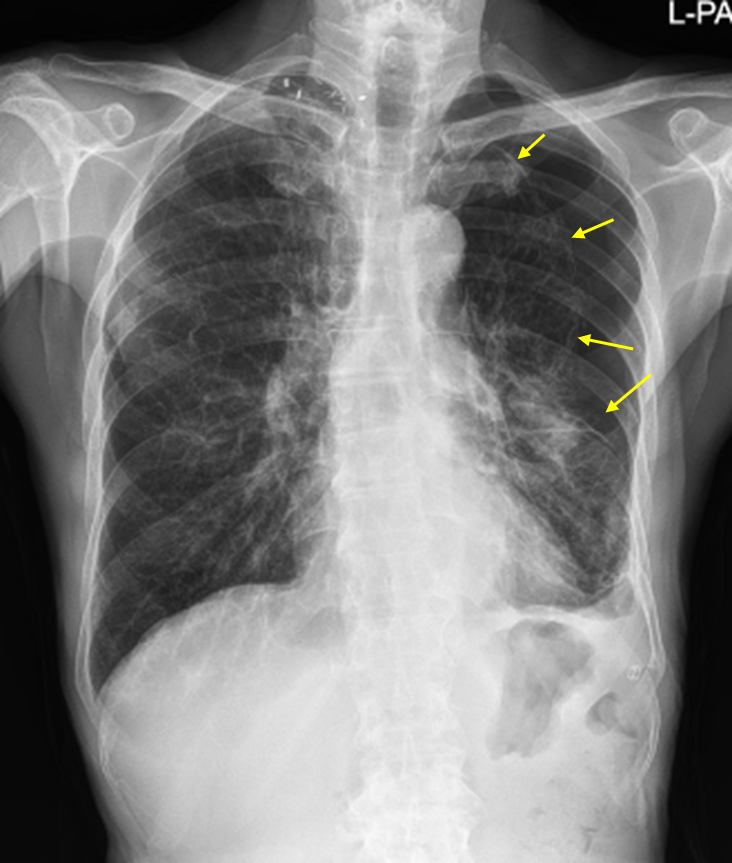

74세 남자가 3일 전부터 숨이 차서 병원에 왔다. 기침하거나 숨을 쉴 때마다 왼쪽 가슴이 답답하다고 한다. 열감이나 가래는 없었다고 한다. 45갑·년의 흡연자이며 만성폐쇄성폐질환으로 치료 중이다. 혈압 130/92 mmHg, 맥박 105회/분, 호흡 24회/분, 체온 36.6℃이다. 청진에서 왼쪽 가슴에서 호흡음이 감소되고, 타진에서 왼쪽 가슴에서 과공명음이 들린다. 가슴 X선 사진이다. 진단은?

Img | CXR: Visceral pleural line in left lung |

임상양상과 CXR의 visceral line으로부터 COPD에 의한 이차성 기흉으로 진단한다.

• 기침하거나 숨을 쉴 때마다 왼쪽 가슴이 답답하고 CXR에서 왼쪽 폐에 visceral pleural line이 보이므로 COPD에 의한 이차성 기흉으로 진단할 수 있다.